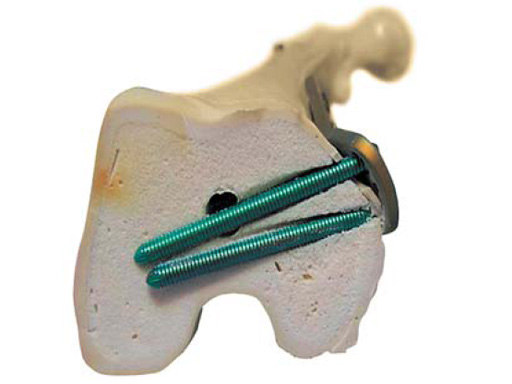

The TomoFix MDF features anatomically preshaped plates with a bending angle of 20. If needed during the operation, this angle can be further bent by using the bending press. The plate profile is 4?mm. The TomoFix MDF is available in a left and right version. The head of the plate offers four isolated LCP holes for 5.0?mm locking head screws. The screw axes of these four LCP holes are converged by 2. Through this alignment a cut-out of the screws can be prevented and the distance to the cruciate ligament is improved. The bolt angulation of 15 in the frontal plane enables use of longer screws and thus a more stable fixation. Bolt placement is easy and safe due to the anatomically adapted shape. The plate shaft features four standard 4.5/5.0 LCP combination holes which are shifted throughout the longitudinal axis. The end of the plate has a bullet nose for use of a MIO technique. Specific guiding blocks for the left and right plates help to insert the drill socket in the correct axis onto the plate.

The plate is inserted distally under the vastus medial muscle after screwing the threaded LCP drill guides into the four distal plate holes using the guiding block. The distal drill holes are oriented in a 20 angle inclination on the frontal plane to avoid a posterior perforation of locking head screws in the distal femur.

An anteromedial skin incision is used. This skin incision can be reused and expanded during subsequent knee surgery. The vastus medialis muscle is dissected from the septum, the medial patellofemoral ligament (MPFL) and the distal insertion of the vastus medialis muscle are partially incised. Two blunt Hohmann retractors are placed around the distal femur. The oblique osteotomy starts in the medial supracondylar area and ends in the lateral condyle, approximately 10 mm inside the lateral cortex. For guiding the closing wedge osteotomy of the distal femur a specific saw guide will be available soon. Alternatively, it is possible to use K-wires inserted under image intensifier control to mark the bone cuts. The saw cuts are made with retractors protecting the soft tissue and vessels. The wedge is removed and the height and depth of the osteotomy can be measured. At this time it is possible to make modifications concerning the wedge size. Closing the wedge must be done gradually by gentle compression of the lower leg laterally, and stabilizing the knee joint medially near the area of osteotomy. This may take several minutes to enable plastic deformation of the lateral cortex to close the osteotomy gap. Leg alignment is checked radiologically after closing with a rigid alignment bar positioned between hip and ankle center. The bar representing the weight-bearing line should pass the preoperatively defined mechanical axis. The plate is inserted from distal under the vastus medialis muscle. The distal drill holes are oriented in a 20 angle inclination on the frontal plane to avoid a posterior perforation of locking head screws in the distal femur. The distal four bolts are placed. A lag screw is positioned in the dynamic hole directly above the osteotomy for compression of the osteotomy site. The screw should be tightened carefully using the image intensifier. The plate is now fixed to the shaft with bolts monocortically, and the lag screw is replaced by a bolt bicortically. The wound is closed in layers after insertion of a drain. The patient is mobilized on the first day after surgery. Partial weight bearing is recommended for 6 weeks, active movement of the knee is enhanced. Biomechanical testing confirmed superior stability of medial closing wedge techniques as compared to lateral open wedge techniques and favourable axial and torsional loading characteristics of the TomoFix medial distal femur (MDF) plate. The plate is now available, as well as a booklet on the operative technique.